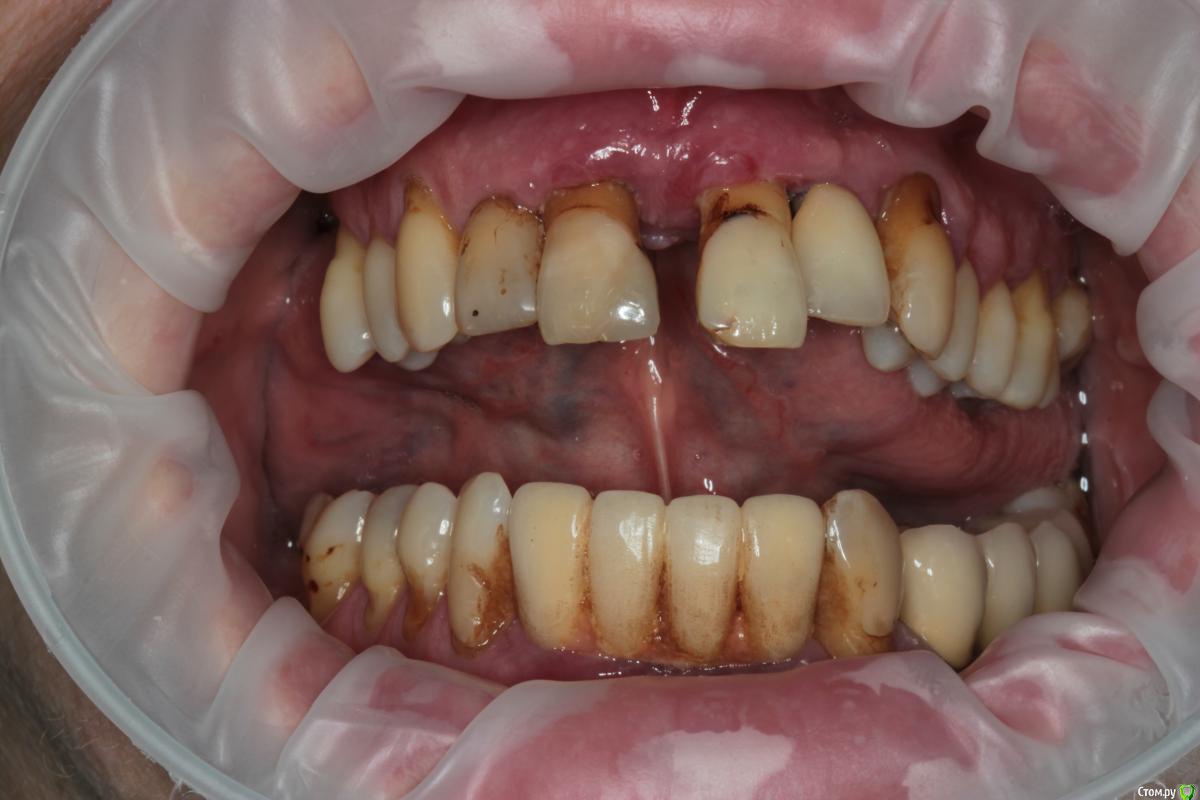

Abuk Опубликовано 27 ноября, 2015 Поделиться Опубликовано 27 ноября, 2015 (изменено) 1.bmp2.bmp3.bmp4.bmpЛечение.Альгинатные слепки,восковая моделировка.Удаление зубов и имплантата,удаление грануляций.Установка имплантатов,заполнение лунок графтом.сст,Времяхи по ключу. Изменено 27 ноября, 2015 пользователем Abuk 13 Ссылка на комментарий

Евгений Ходыкин Опубликовано 29 ноября, 2015 Поделиться Опубликовано 29 ноября, 2015 Фото перед операцией? Гигиена ужас конечно... Ссылка на комментарий

Abuk Опубликовано 29 ноября, 2015 Автор Поделиться Опубликовано 29 ноября, 2015 (изменено) 1 е фото -"до", после были слепки и гигиена.Непосредственно перед имплантацией нет.Гигиена не фонтан,условились на том что первый год приходит каждые 3 месяца(осмотр и ггигиена),а там далее смотрим. Изменено 29 ноября, 2015 пользователем Abuk Ссылка на комментарий